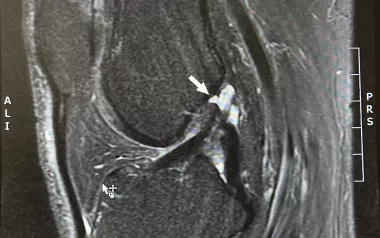

Copers are people who can return to full activity after an ACL injury. ACL surgery is effective at reducing joint laxity; however, there is no difference in joint laxity between copers and noncopers. Noncopers can become copers through training, with proprioception, strength, and expectations about recovery being the most significant factors that distinguish copers from noncopers.